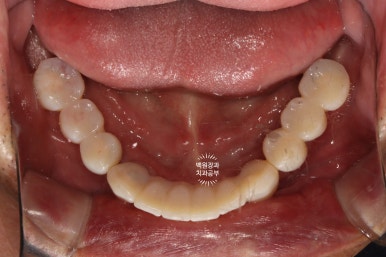

아래턱 임플란트 수술을 하였습니다.

아래턱 치아 12개를 만들어드리는데, 6개의 임플란트만 있으면 됩니다.

약 2주 정도 지나서 아래턱 임플란트 6개를 심어드렸습니다.

위턱의 경우 아까 언급하였듯, 임플란트가 심어질 잇몸뼈가 아래턱에 비해 무르기에 보다 많은 임플란트를 필요로 하지만, 아래턱의 경우 전체 임플란트를 위한 최소한의 임플란트 개수는 6개입니다.

송곳니 2개, 작은어금니 2개, 큰어금니 2개 총 6개의 임플란트만 있으면, 아래 완전틀니를 안쓰시게 될 수 있죠.

좌측이 위턱, 오른쪽이 아래턱입니다.

확인하실 수 있듯, 아래턱의 경우 단 6개의 임플란트만 심었음에도 불구하고, 총 12개의 치아를 만들어드릴 수 있었습니다. 위턱의 경우 좌측 3개, 우측 1개의 임플란트로 총 5개의 치아를 만들어드린 상태입니다.